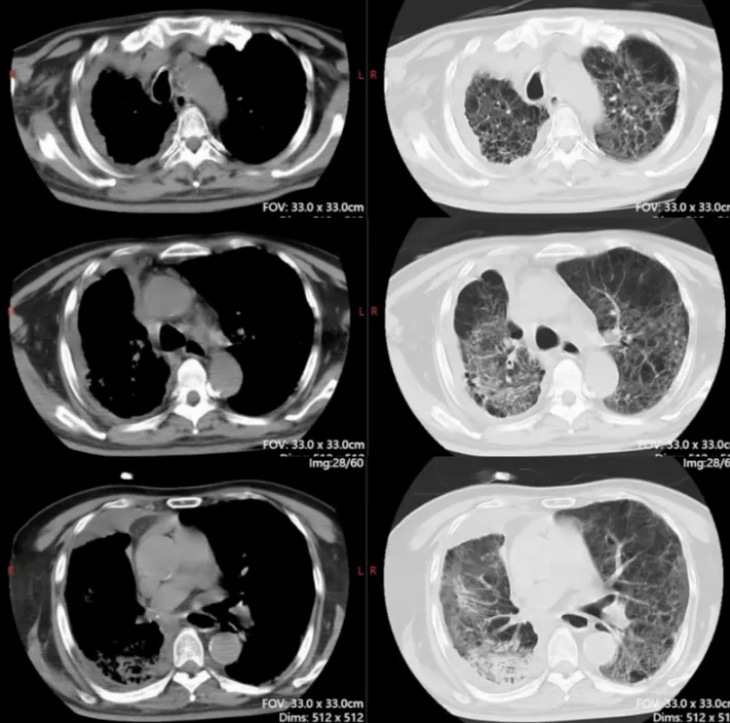

复查胸部CT(2021-12-27):右肺有大片蜂窝状改变,右下肺有脓胸、空洞及纵隔脓肿(图6)。

图6 复查胸部CT(2021-12-27)